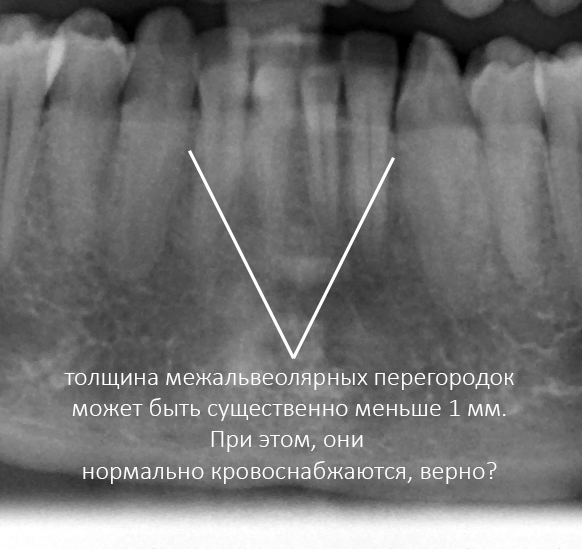

Для начала, снова покажу картинку с межальвеолярными перегородками во фронтальной группе:

Их толщина существенно меньше миллиметра. Но, при этом зубы стоят, верно? Никакой убыли костной ткани не происходит. До тех пор, пока зубы стоят правильно, без излишней нагрузки. Но при патологии прикуса, скученности зубов, нагрузка на нижние резцы (и, следовательно, костную ткань) возрастает. Это называется — «превед, пародонтит!», прогрессирует атрофия костной ткани в области перегруза.

Что за фигня? Дело в том, что до тех пор, пока нагрузка на кость распределяется равномерно, костная ткань нормально кровоснабжается. Стоит её перегрузить, как «в тонких участках» возникает ишемия со всеми вытекающими. Они просто сжимаются, перекрывая ток крови по микрососудистому руслу. Нет кровоснабжения — нет питания. Нет питания — «превед, пародонтит!». Всё относительно просто.